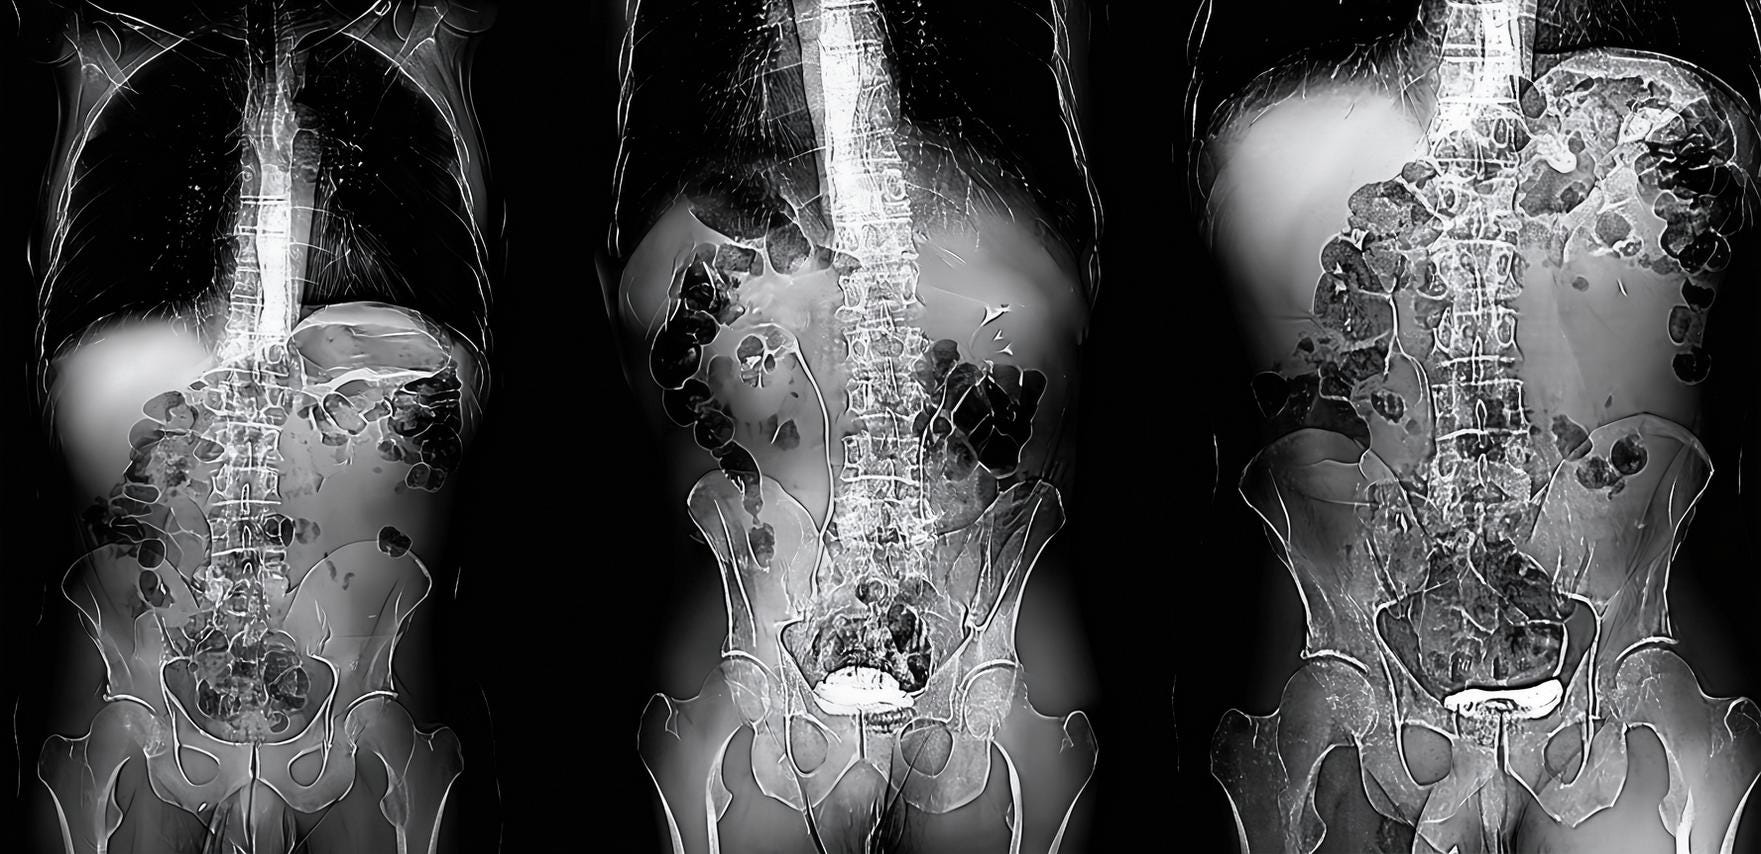

This post concerns an impending death; my own. My recent diagnosis (Mar 4ᵗʰ) is both complicated, but also typical of a stage four lung cancer (metastatic cancer), if I understand it right, with the cancer identifying itself only weeks ago, and further growths identified since then: I have tumours in the legs, lymph nodes and adrenal glands; a 4.5 cm tumour on the left lung is crowding out the nearby aorta; it has sprouted a smaller (11 mm) tumour on the right lung too; and colonies have set up camp in the cerebellum. A round of CT (Computed Tomography), MRI (Magnetic Resonance Imaging), X-Ray, EBUS (Endobronchial Ultrasound), and PET (Positron Emission Tomography) scan results is still being analysed. New facts emerge. I’m only just weeks into things and counting.

A PET scan is organised a few days later, at St Barts Hospital, in the shadow of St Paul’s. The body is flooded with a tracer radioactive fluid, after which you are locked into a lead-lined box for three-quarters of an hour to allow it to bake in. The scanner then detects where the tracer has been absorbed by cell growth anywhere in the body it is directed, producing reams of flowing light captured to film, copies of which—scans of my own body—are used throughout this post.

The moment I saw the very first scan the doctors showed me (bottom right, above: an MRI, rather than PET, as it happens)—on a small monitor wheeled into my cubicle at the Homerton—seemed to say everything at once. As I turned my head to look at the image of my brain on the monitor, I glimpsed also the tattoo on my left arm suddenly aligned with it (bottom left)—a tattoo of a bhikkhu meditating in flames, inked twenty years earlier, with the bhikkhu meditating as descibed in the Buddha’s Adittapariyaya Sutta (Fire Sermon)—such that the tattoo of the bhikkhu and the scan of the brain, aligned properly. One presaged the other by years, holding out its hand to the other. They reflected each other so neatly, with the tumour in the cerebellum showing up as the red-orange fire bursting through from within, which the bhikkhu sits through.

On seeing further scans, I recognised, eg., my rib cage as something indeed very much like the frame of Israel’s tents (above, top left), beaming on the shore of the infinite (Blake), but also, in the twisting images of the torso, I am struck by the sprawling energies at play, unleashed by disease. No longer is there the assumed underlying durable person, sealed away from the totality, cybernetically establishing their personal border by fending off and repurposing the chaos, sickness and disorder without. Instead, raw energies start to coalesce, turning Urizenic, mechanical rigidity into flashes, streaks and pulses of contending light.